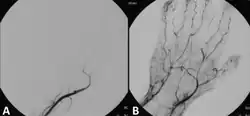

- rychle a razantně rozpouštět trombolýzou

- odstranit mechanicky katetrizací.